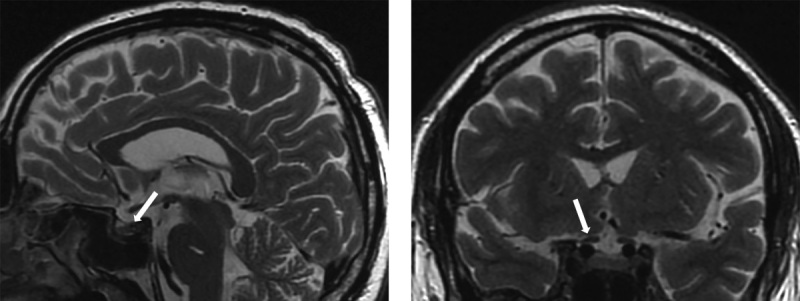

近年来,自身免疫性内分泌疾病的发病率大幅上升,众所周知,这些疾病会影响包括垂体在内的各级内分泌系统。垂体炎是一个通用术语,用于描述任何形式的蝶鞍和蝶鞍上炎症,这些炎症会导致下丘脑-垂体区域的结构发生变化,并表现为垂体前叶和垂体后叶不同程度的激素缺乏。迄今为止,垂体下腺炎有原发性和继发性之分,原发性垂体下腺炎是由于垂体直接遭受自身免疫性病变所致,而继发性垂体下腺炎则是由于存在全身性自身免疫性疾病所致。无论病因如何,垂体功能减退症患者都会表现出由垂体炎症过程引起的各种体征和症状,从而导致垂体功能减退、蝶鞍和蝶鞍旁结构受压。磁共振成像是目前诊断垂体功能减退症的最佳非侵入性诊断工具,但只有通过垂体组织的组织学检查才能确定诊断,而组织学检查需要侵入性方法,这就大大降低了该手术的可行性。在本文中,我们介绍了一名在没有明确临床症状的情况下,核磁共振成像显示有垂体功能减退症迹象的患者。

In recent years, there has been a significant increase in the prevalence of autoimmune endocrinopathies, which are known to affect various levels of the endocrine system, including the pituitary gland. Hypophysitis is a general term used to describe any form of sellar and suprasellar inflammation that leads to structural changes in the hypothalamic-pituitary region and manifests itself in varying degrees of hormonal deficiency of the anterior and posterior pituitary glands. To date, there is a primary form of hypophysitis, which occurs as a result of an autoimmune lesion directly to the pituitary gland, and a secondary form of hypophysitis, which occurs as a result of the presence of a systemic autoimmune disease. Regardless of the etiology, patients with hypophysitis show various signs and symptoms caused by an inflammatory process in the pituitary gland, which can lead to the development of hypopituitarism, compression of the sellar and parasellar structures. MRI is currently the best non-invasive diagnostic tool for diagnosing hypopituitarism, however, the diagnosis can be made with certainty only by histological examination of the pituitary tissue, which requires an invasive approach, which greatly reduces the feasibility of this procedure. In this article, we present a patient with MRI showing signs of hypophysitis in the absence of clear clinical symptoms.